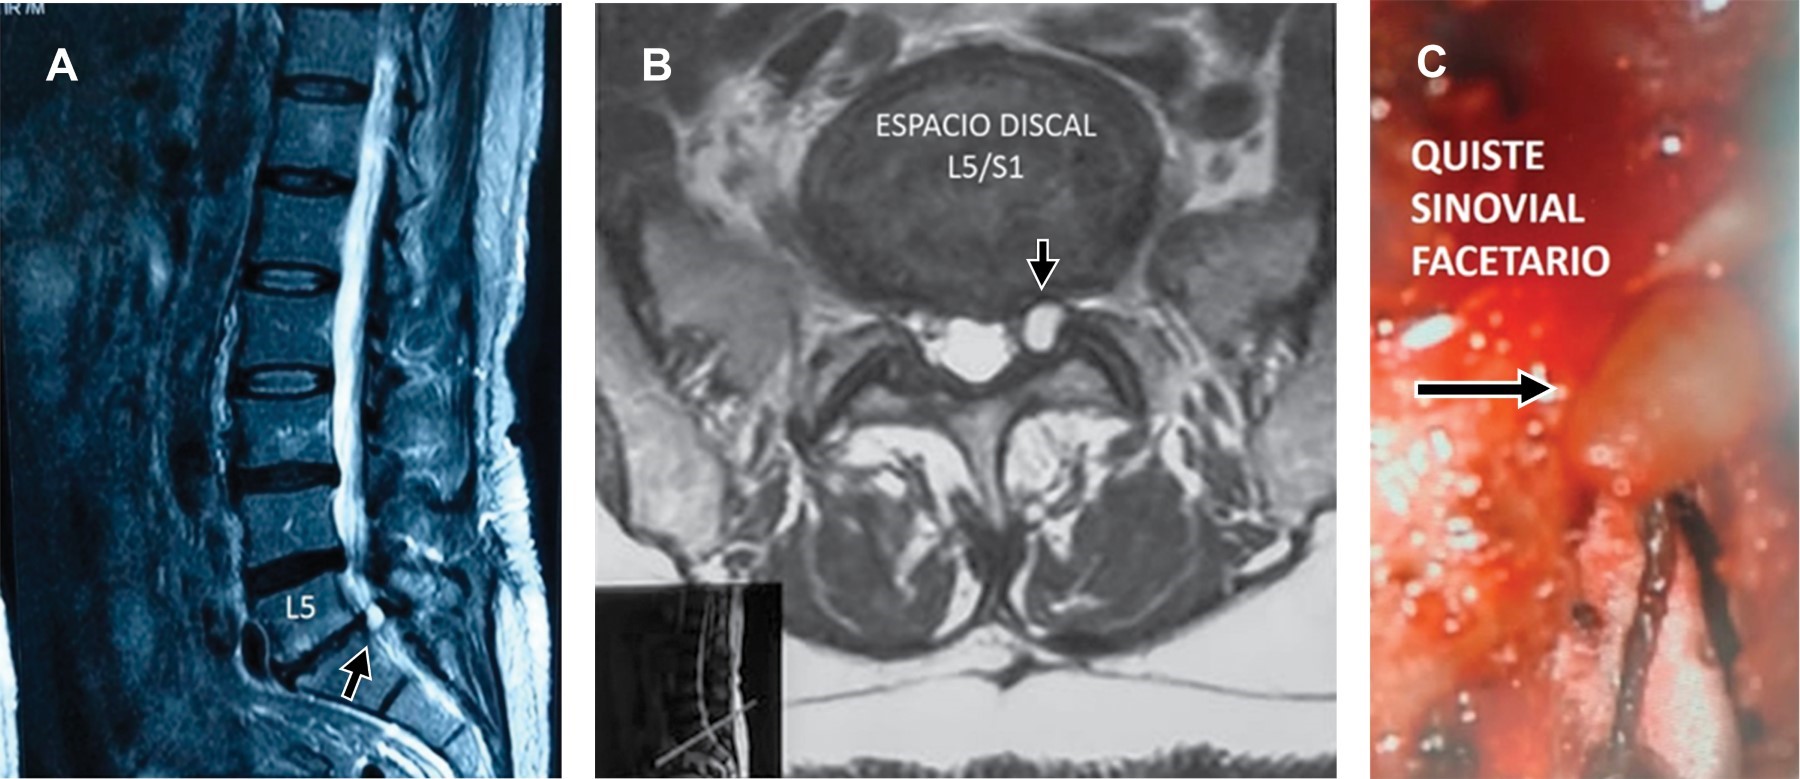

Compresión radicular L5/S1 por quiste sinovial facetario

Masculino de 55 años acude por lumbalgia con compresión radicular S1 izquierda de un mes de evolución (Figura 1). Los quistes sinoviales facetarios (QSF) son lesiones degenerativas intraespinales y extradurales que se originan de la cápsula de la articulación facetaria; tienen una incidencia de 0.002 a 0.8%; se localizan (68.4%) a nivel de L4/L5; (21%) en L5/ S1; y 5% tanto en L1/L2 como en L2/L3. La serie más grande que se ha reportado es 194 casos. Los QSF se desarrollan por alteraciones biomecánicas; la presencia de espondilolistesis en 33% de los casos y la hipermovilidad en 60% de los pacientes son el principal factor etiológico en su formación. La mayoría de los pacientes con QSF se encuentran en la sexta década de la vida, con predominio femenino con relación 2:1. En la última década, con la resonancia magnética nuclear (RMN) se han incrementado los reportes. Los síntomas más comunes en QSF son: radiculopatía dolorosa (85%), claudicación de una raíz (44%), alteraciones de sensibilidad (43%) y paresia (en 27% de los casos), aunque también pueden presentarse manifestaciones de claudicación intermitente por estenosis espinal y más raramente síndrome de cauda equina (1-13%). Para su tratamiento, la cirugía ha demostrado ser el tratamiento definitivo; sin embargo, existen reportes de resolución con aspiración percutánea.

Figura 1